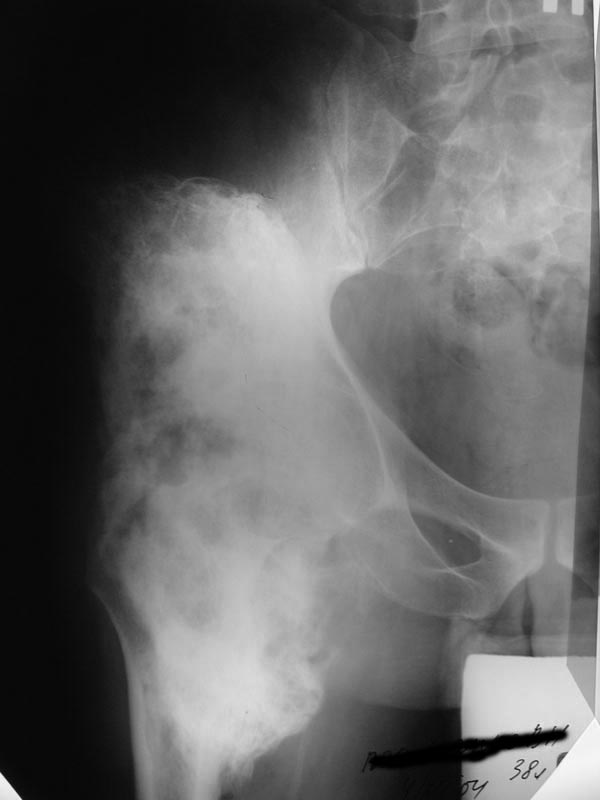

Мужчина 38 лет, Х.В.Н., диагноз: Закрытый травматический компрессионно-оскольчатый перелом L1 позвонка, вывих Тh 12, ушиб, сдавление спинного мозга, нижняя параплегия, нарушение функции тазовых органов. Операция 01.07.03: ламинэктомия Th 12-L1, задний спондилодез проволокой с протакрилом.06.11.03 -- удаление протакрила, ламинэктомия Th 12-L1, декомпрессия спинного мозга, менингомиелолиз.У больного, как проявление нейродистрофического синдрома, сформировались грубые оссификаты вокруг обоих тазобедренных суставов с резким ограничениемдвижений.14.01.04 – операция иссечения переднебоковых оссификатов правого тазобедренного сустава. На операции достигнуто сгибание около 85 град. Впослеоперационном периоде потеря коррекции значительна (более 50%).На сегодняшний день: Больной лежит, движения в тазобедренных суставах отсутствуют. По передней поверхности обоих суставов пальпируются плотныеопухолевидные образования 6 х 8 см.На R-граммах: обширные оссификаты по передней и боковой поверхности т/бедренных суставов (см. приложенные файлы).Планируется оперативное лечение: иссечение оссификатов.Больного необходимо посадить в кресло-каталку для дальнейшей реабилитации.У кого есть предложения?Направление пациента на лечение согласовано с Министерством здравоохранения Хабаровского края, финансирование обещано.Лечащий врач Е.В.Квитченко